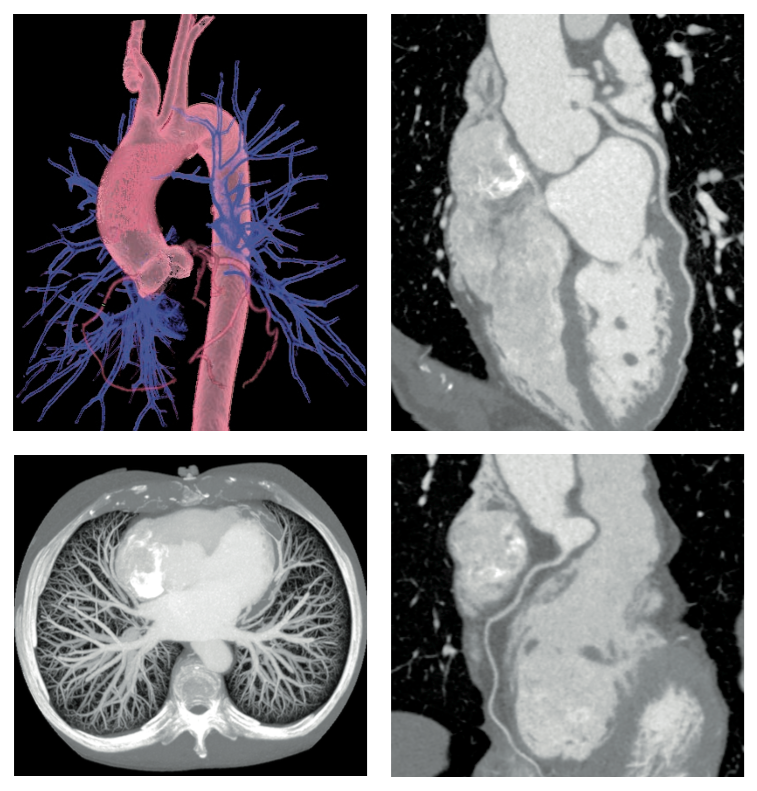

revolution ct临床病例5——完美的胸痛三联检查

图片尺寸757x791